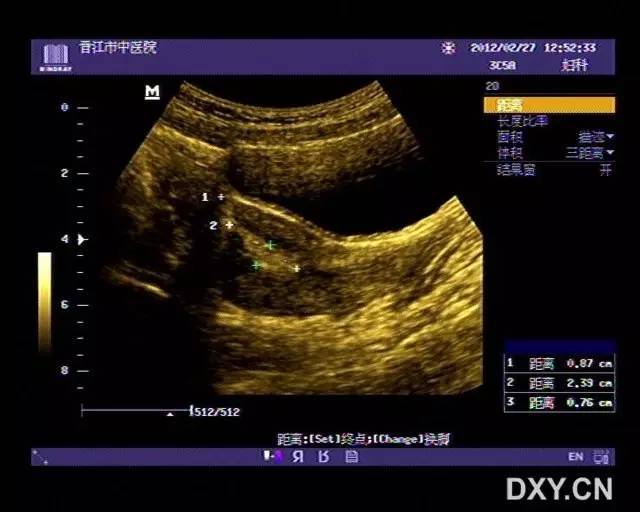

子宫穿孔超声表现图

子宫穿孔超声表现图,子宫穿孔超声图片

超声典型病例子宫穿孔

子宫穿孔的超声诊断

高手进阶:子宫穿孔的超声诊断

子宫穿孔超声图片

子宫穿孔彩超下表现

子宫穿孔彩超图

子宫穿孔b超图片